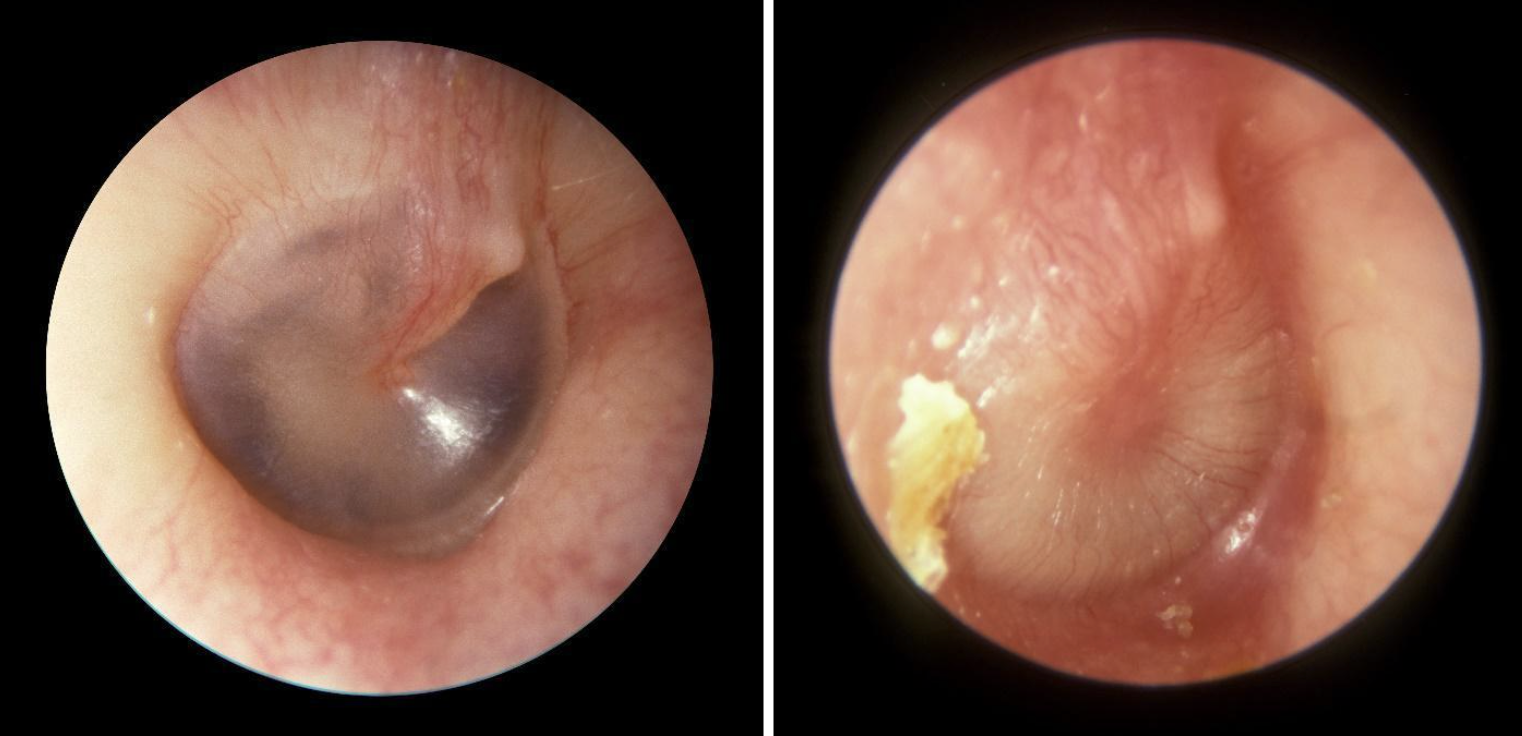

Figure: Normal tympanic membrane (left) vs acute otitis media (right). Image courtesy of Michael Hawke, MD.

On otoscopic exam, it is important to remove cerumen via irrigation or manual extraction to clearly check the TM for color, opacification, position, and mobility. The TM is normally a translucent pearly gray with visible landmarks. The TM of AOM can be erythematous, cloudy, immobile, and must be bulging. The clinical history for otitis externa (OE) may be more helpful. There may be a history of swimming, scratching, or excessive cleaning. OE commonly presents with otalgia, pruritis, conductive hearing loss, tinnitus, or discharge.